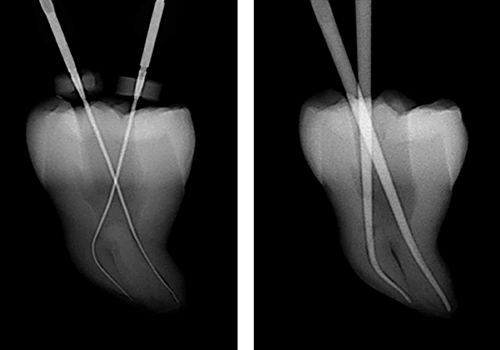

根の治療は手探りで行うため、根の治療の成功率は専門医でなければ50%を切ると言われています。

トライオートZX2という器械は、柔軟性のある特殊のファイルを使用するため、目では見えない複雑な形態の根管を傷つける事なく短時間での治療が可能です。

そのため患者様負担は軽減され、治療の成功率を飛躍的に上げることが可能です。根の治療をあきらめていた方も一度ご相談ください。